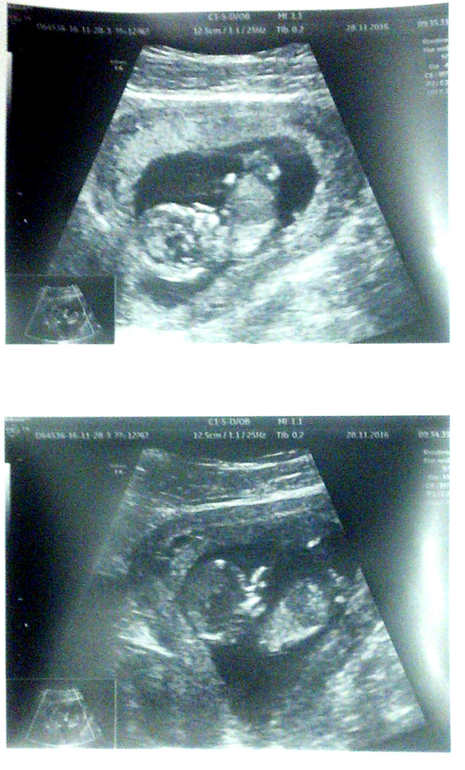

Первый скрининг! ^_^ Впечатления!

походу на таком сроке все спортсмены, мой на велосипеде воображаемом ехал, ногами крутил и руками, еле споймали чтоб параметры вымерять.

Не хотел скриниться? ^_^ Бывает такое от волнения. Я ещё видела, как они личико руками закрывают. У меня за 15-20 секунд видео (что мне показали) он успел повернуться спинкой и опять бочком, лечь на спинку и перевернуться головкой вниз) ни секунды не сидел на месте. Я тоже была поражена)

13 полных акушерских?

Да, завтра 14-я начнётся :)

Вообще) Мой успел повернуться спинкой и вернуться в боковое положение за каких-нибудь 15 секунд :) и всё это время шевелил ручками, ножками, головой, просто плавал и становился то вниз головой, то вниз спинкой=) Это так мило, даже не верится немного, что внутри меня всё происходит.